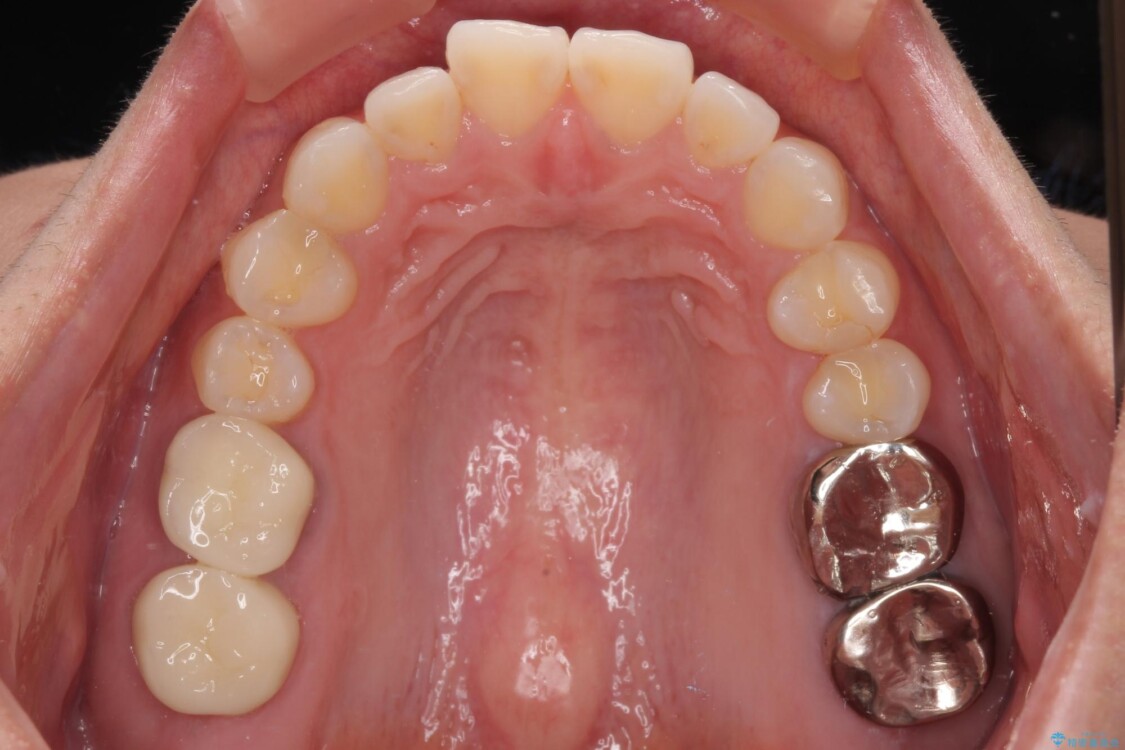

スペースが整った段階で、右下の第一大臼歯と第二大臼歯にインプラントを埋入。

その後、挺出していた右上第一大臼歯と第二大臼歯に装着されていた銀歯についても、審美性と適合性の向上を目的に、オールセラミッククラウンにやり替えました。

これにより、より自然で美しい見た目と、高い精度の咬合が得られています。

治療後

• 挺出歯を圧下してスペースを確保!目立たない部分矯正で下顎大臼歯にインプラント治療を実現 治療後画像